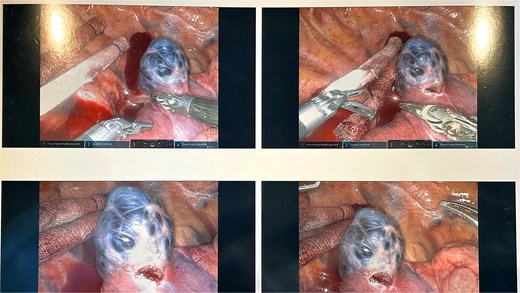

A 45-year-old female with past medical history of hypertension and unspecified connective tissue disorder presented to the emergency room with leg pain, chest pain, and dyspnea with initial blood pressure of 197/138 due to medication noncompliance. Due to the constellation of symptoms combined with severe hypertension, CT chest was ordered to rule out aortic dissection. The scan did not show aortic dissection but incidentally found 4 cm azygos vein aneurysm. The patient had resolution of symptoms, blood pressure was control with medications, and she has been followed outpatient for the azygos vein aneurysm with conservative management of daily aspirin and annual CT thorax scans for 4 years. Four years later, she presented to our clinic with no symptoms of chest pain, dyspnea, cough, and so on but wanted to discuss surgical options. Her most recent CT thorax revealed a stable azygos vein aneurysm measuring 4 cm (Fig. 1). After discussing the risks and benefits of surgery, the patient consented to surgical resection. The patient then underwent robotic assisted mediastinal mass resection with no complications. The intra-operative findings included a hemorrhagic multi-cystic appearing lesion which was connected to the azygos vein as well as the apex of the right lung (Fig. 2). This lesion was isolated with electrocautery and blunt dissection; proximal and distal control of the azygos vein were transected with a surgical stapler and chest tube was placed (Fig. 3). Postoperatively, patient recovered well, chest tube was removed, and she was discharged home on postoperative day one. Surgical pathology was benign and revealed a portion of lung parenchyma with associated dilated blood vessels. She is doing well and has no cardiac or pulmonary symptoms 2 years after surgery.

The intra-operative findings included a hemorrhagic multi-cystic appearing lesion which was connected to the azygos vein as well as the apex of the right lung.

This lesion was isolated with electrocautery and blunt dissection; proximal and distal control of the azygos vein were transected with a surgical stapler.